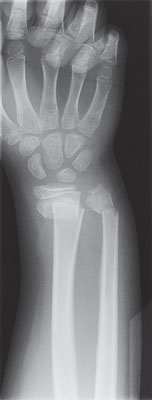

A bone X-ray is a way to take pictures of bones. It may also be called bone radiography. In this test, a low dose of radiation is passed through the body, producing digital images of the bones or images on a piece of film.

X-rays of bones may be taken to:

Find breaks or chips (fractures) in the bones.